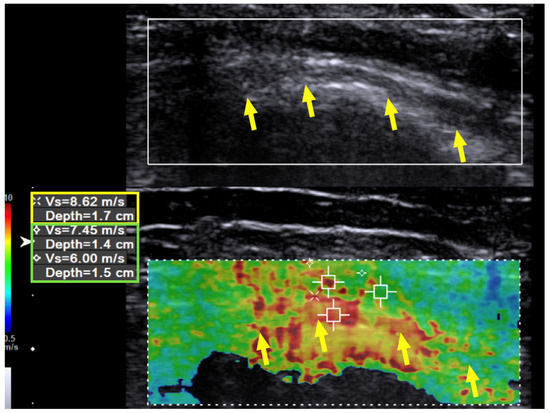

Case 1: A 31-year-old man sustained a left humeral shaft fracture in a traffic accident and underwent fixation with a dynamic compression plate. Fourteen months later, the plate was removed, after which the patient developed a wrist drop of his left hand. Neurodiagnostic studies (i.e., nerve conduction velocity and electromyography) were performed two months after the surgery and showed severe axonal damage with no signals from the radial nerve. Spontaneous activity was noted over the supinator, extensor carpi radialis longus (ECRL), extensor digitorum communis (EDC), and extensor indicis proprius (EIP) muscles, without any motor unit action potentials (MUAP) during recruitment. The ultrasound (US) examination showed a continuous radial nerve with an increased CSA and hypoechoic changes to the nerve fascicles at both the entrance to the spiral groove and supinator levels. Our US system (Acuson S3000, Siemens Healthcare (Pty) Ltd., Erlangen, Germany) entails a linear-array transducer with a bandwidth of 4–9 MHz. The SWV of the radial nerve was assessed using dedicated software (Virtual Touch Tissue Imaging Quantification (VTIQ), Siemens Healthcare (Pty) Ltd., Erlangen, Germany). With the VTIQ software, SWV can be assessed from 0–10 m/s. Segment-by-segment SWE was performed over the course of the radial nerve in the left upper arm, and increased hardness (SWV = 9.94 m/s) was identified at the entrance to the spiral groove, where the nerve starts to wrap around the humerus (Figure 1). The SWV of the contralateral side was 4.05 m/s (Figure 2).

Figure 1. Case 1: Shear wave velocity before hydrodissection. Shear wave velocity (SWV) investigation of the radial nerve over the spiral groove before hydrodissection in a 31-year-old man with wrist drop following plate removal after humerus fracture osteosynthesis. Multiple regions of interest are selected, including the radial nerve and the surrounding tissues. The SWV of the radial nerve is 9.94 m/s and that of the surrounding soft tissue is 10 m/s. Yellow arrow and box: radial nerve in longitudinal view. Green box: scar tissue.